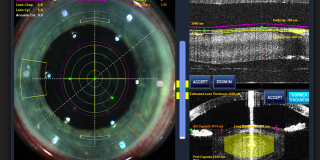

La chirurgia della cataratta ha subito notevoli evoluzioni tecnologiche. L’introduzione del Laser a Femtosecondi o Femto Laser ha letteralmente rivoluzionato questa chirurgia. Grazie ad esso le fasi principali dell’intervento vengono programmate dal chirurgo al computer ed effettuate dal laser in pochi secondi senza l’utilizzo di bisturi e pinze. Tutti i passaggi sono monitorati in tempo reale attraverso un controllo tridimensionale mediante OCT delle strutture oculari, guidando l’azione del laser.